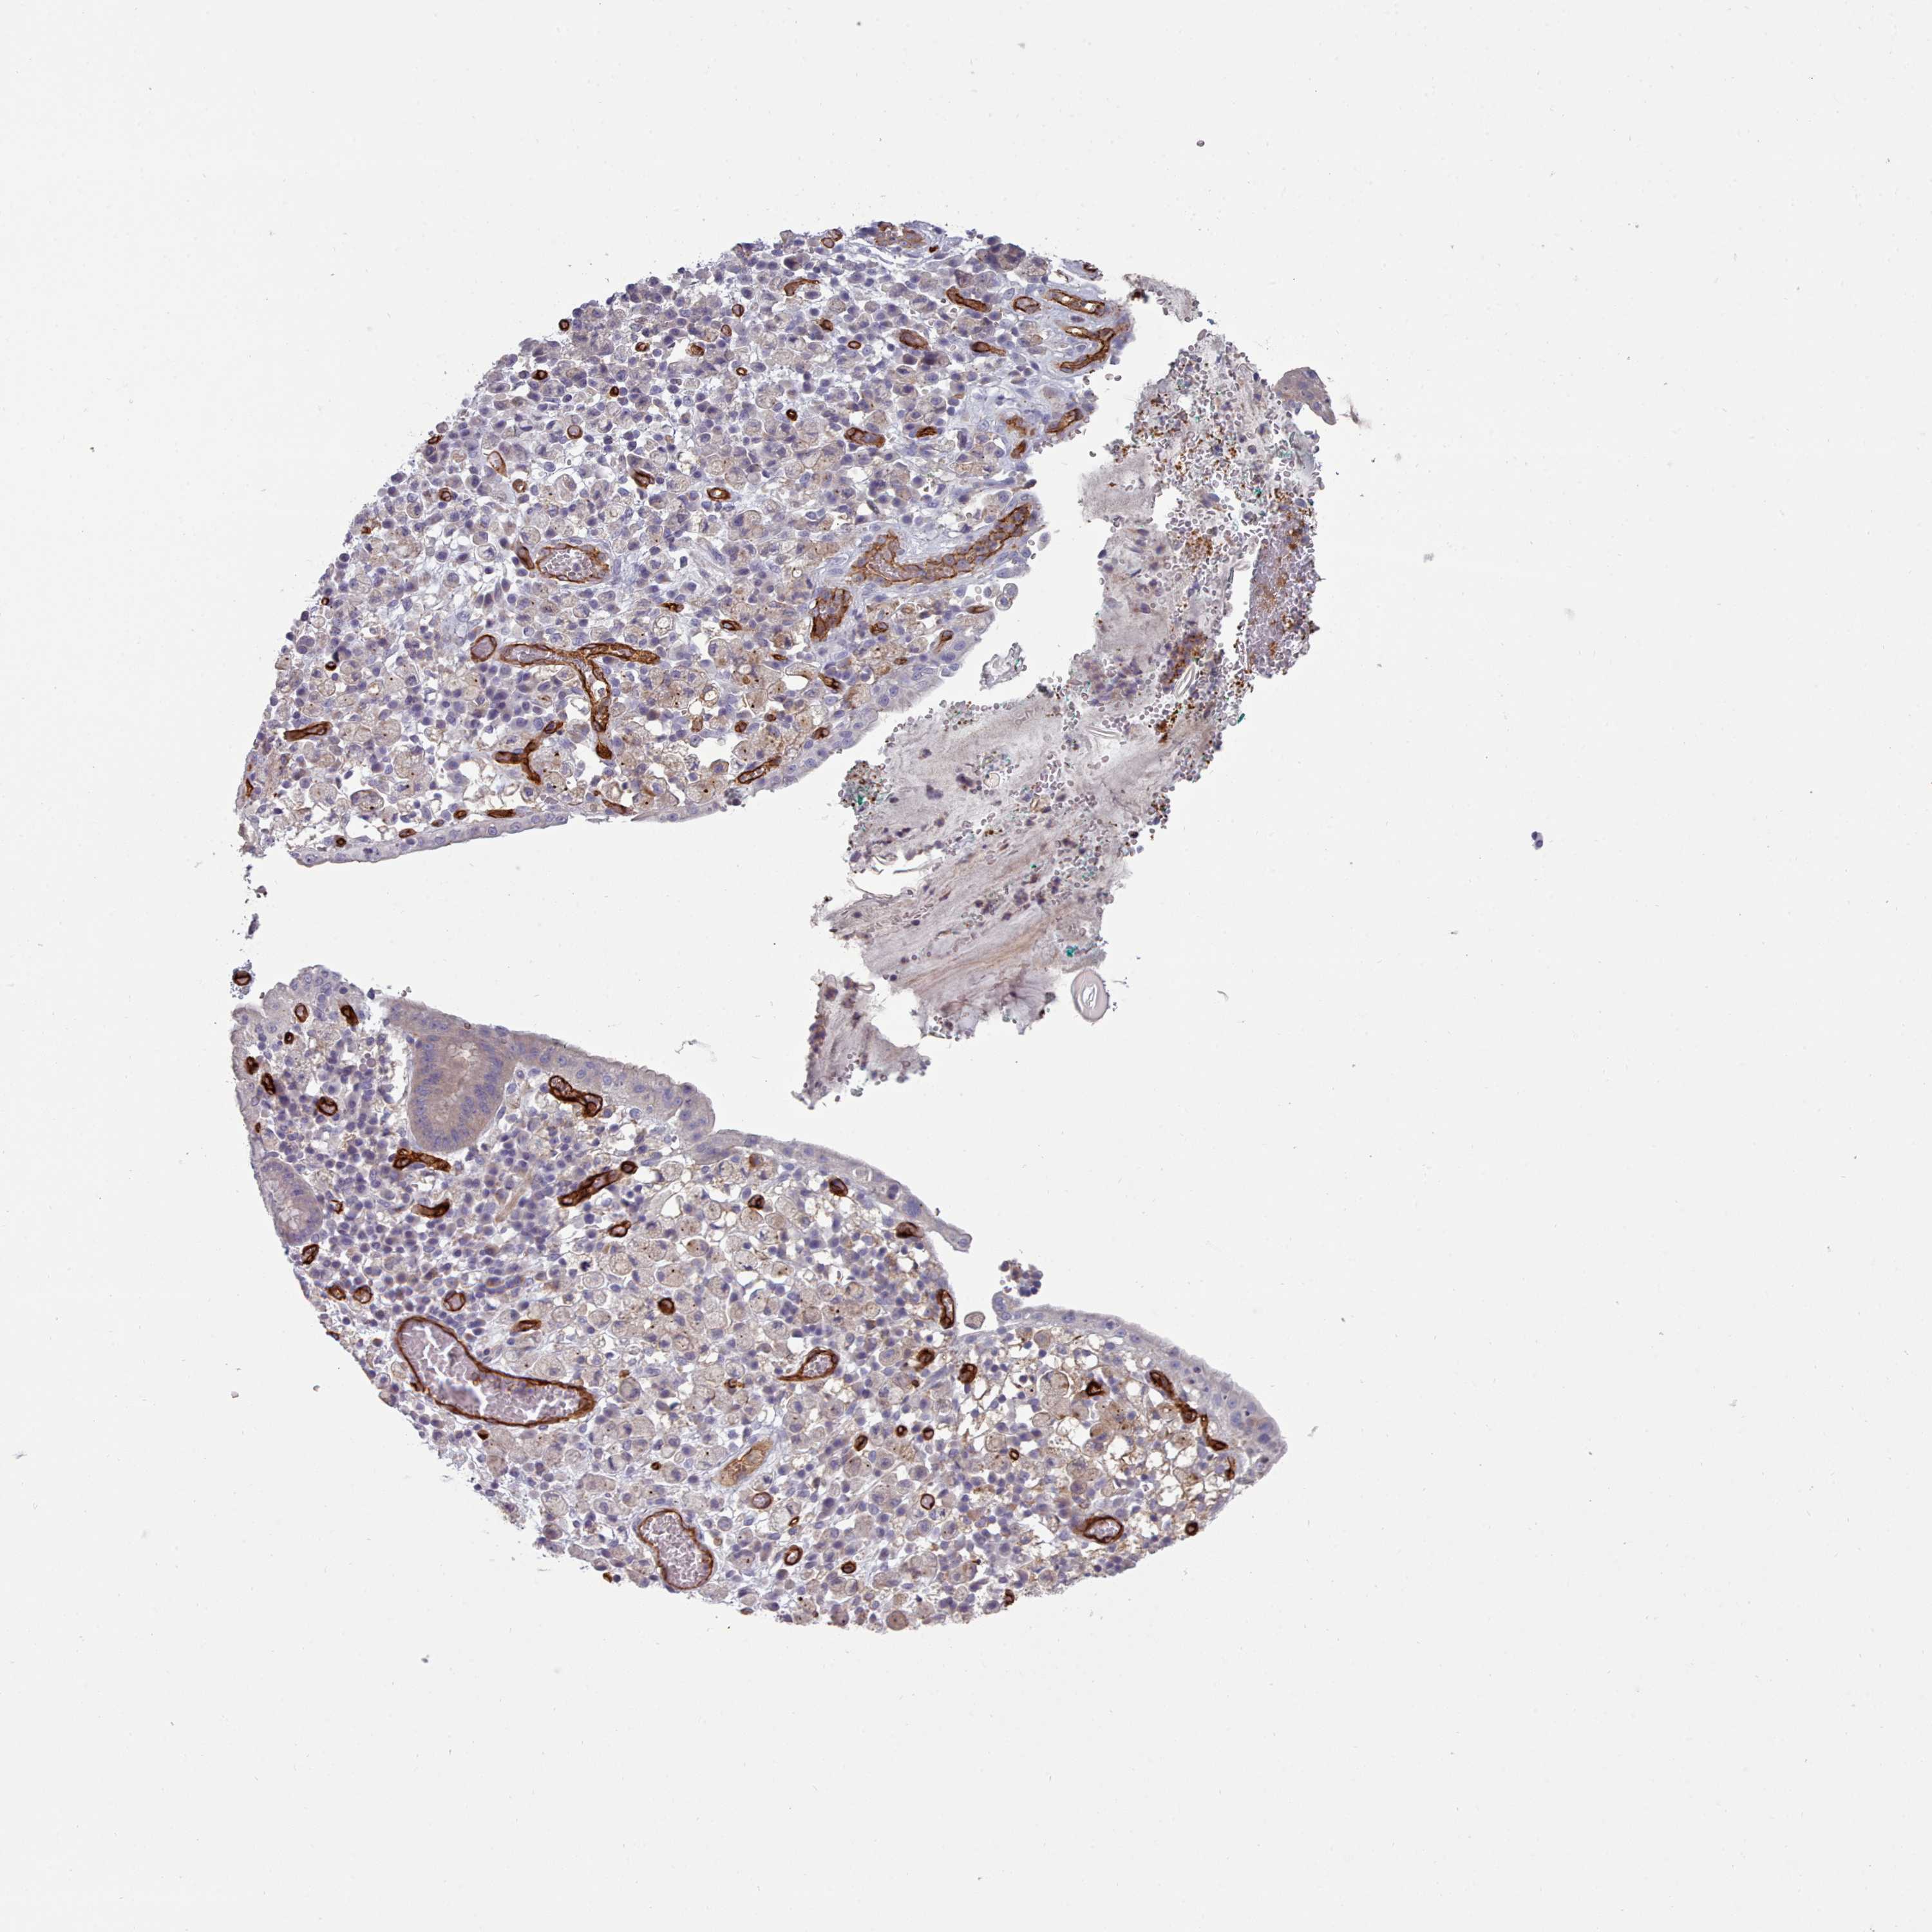

STOMACH CANCER - Protein expressioni

A mouse-over function shows sample information and annotation data. Click on an image to view it in a full screen mode. Samples can be filtered based on level of antibody staining by selecting one or several of the following categories: high, medium, low and not detected. The assay and annotation is described here.

Note that samples used for immunohistochemistry by the Human Protein Atlas do not correspond to samples in the TCGA dataset.

Antibody stainingi

Antibody staining in the annotated cell types in the current human tissue is reported as not detected, low, medium, or high, based on conventional immunohistochemistry profiling in selected tissues. This score is based on the combination of the staining intensity and fraction of stained cells.

Each image is clickable and will lead to virtual microscopy that enables deeper exploration of all samples and also displays staining intensity scores, fraction scores and subcellular localization as well as patient and tissue information for each sample.

Antibody HPA013712

Staining

High

Medium

Low

Not detected

Intensity

Strong

Moderate

Weak

Negative

Quantity

>75%

75%-25%

<25%

None

Location

Nuclear

Cytoplasmic/membranous

Cytoplasmic/membranous,nuclear

Adenocarcinoma, NOS